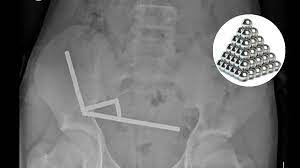

The New Zealand teenager, whose identity was not disclosed, ingested an estimated 80 to 100 neodymium magnets, each measuring just five millimeters by two millimeters. These high-powered magnets, often marketed as desk toys for adults, pose a grave threat if swallowed.

The strong magnetic pull of the ingested magnets caused severe internal complications. After enduring four days of abdominal pain before seeking help, scans revealed the magnets had clustered into four chains, forcibly pulling together different sections of his bowel and large intestine.

This magnetic compression led to pressure necrosis, tissue death from prolonged pressure—in parts of his digestive tract. Such pressure can cause perforation or life-threatening infections.